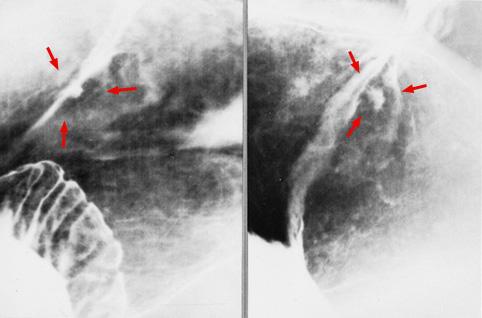

질환(병리주체)의 분류 악성 상피성종양/선암

부위(장기별) 위(부위)/분문

검사방법 X-P

종양의 육안분류 0형(표재형)/IIc형(IIc)

종양의 최대경(밀리미터) 10~14

종양의 심달도 m